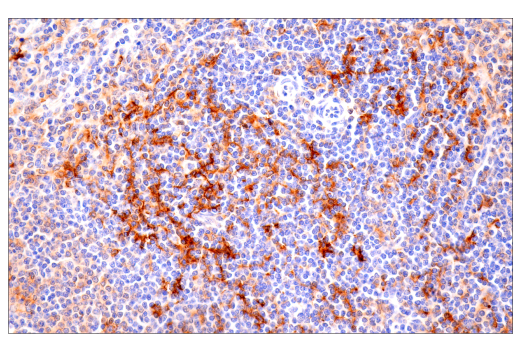

W, IHC-Bond, IHC-P, IF-IC

W: Western Blotting IHC-Bond: IHC Leica Bond IHC-P: Immunohistochemistry (Paraffin) IF-IC: Immunofluorescence (Immunocytochemistry)